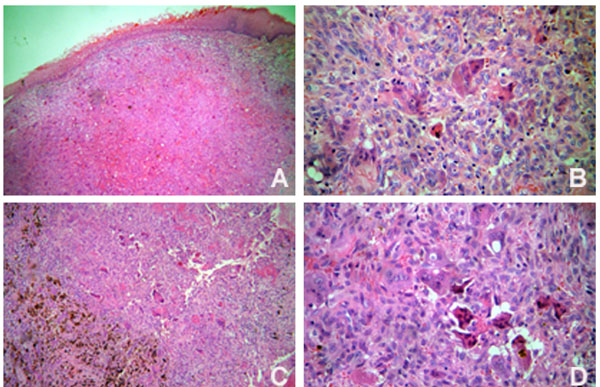

The patient underwent comprehensive non-surgical periodontal therapy. Teeth 26, 28, 36, 37, 46 and 48 were removed due to advanced periodontal disease. Based on a provisional diagnosis of pyogenic granuloma or peripheral giant cell granuloma, the anterior hyperplasic lesion was entirely removed through excisional biopsy. Histological examination confirmed the diagnosis of peripheral giant cell granuloma (Fig. 3A and 3B). In the posterior intra-osseous lesion, a fine needle aspiration biopsy was performed, but it was not contributive. Thus, an incisional biopsy was done and the time teeth 46 and 48 were extracted. The histological diagnosis was central giant cell granuloma (Fig. 3C and 3D). The parathyroid hormone level was within the normal limits. After a discussion with the medical staff on how to approach the case, the intraosseous lesion was conservatively treated. A total volume of 0,5 ml injections of corticosteroid (triamcinolone, 20 mg/ml) and local anaesthetic solution (lidocaine 2%, 1:1) [12, 13] were used. Intralesion applications were performed every fifteen days for three times. Two weeks after the third application, clinical and radiographic examinations suggested regression of the lesion and no further applications were necessary. There was no evidence of recurrence after 1 year of follow-up.

Histopathological features of the peripheral (A and B) (Original magnification x 100 and x 400, respectively) and central giant cell lesions (C and D) (Original magnification x 100 and x 400, respectively).